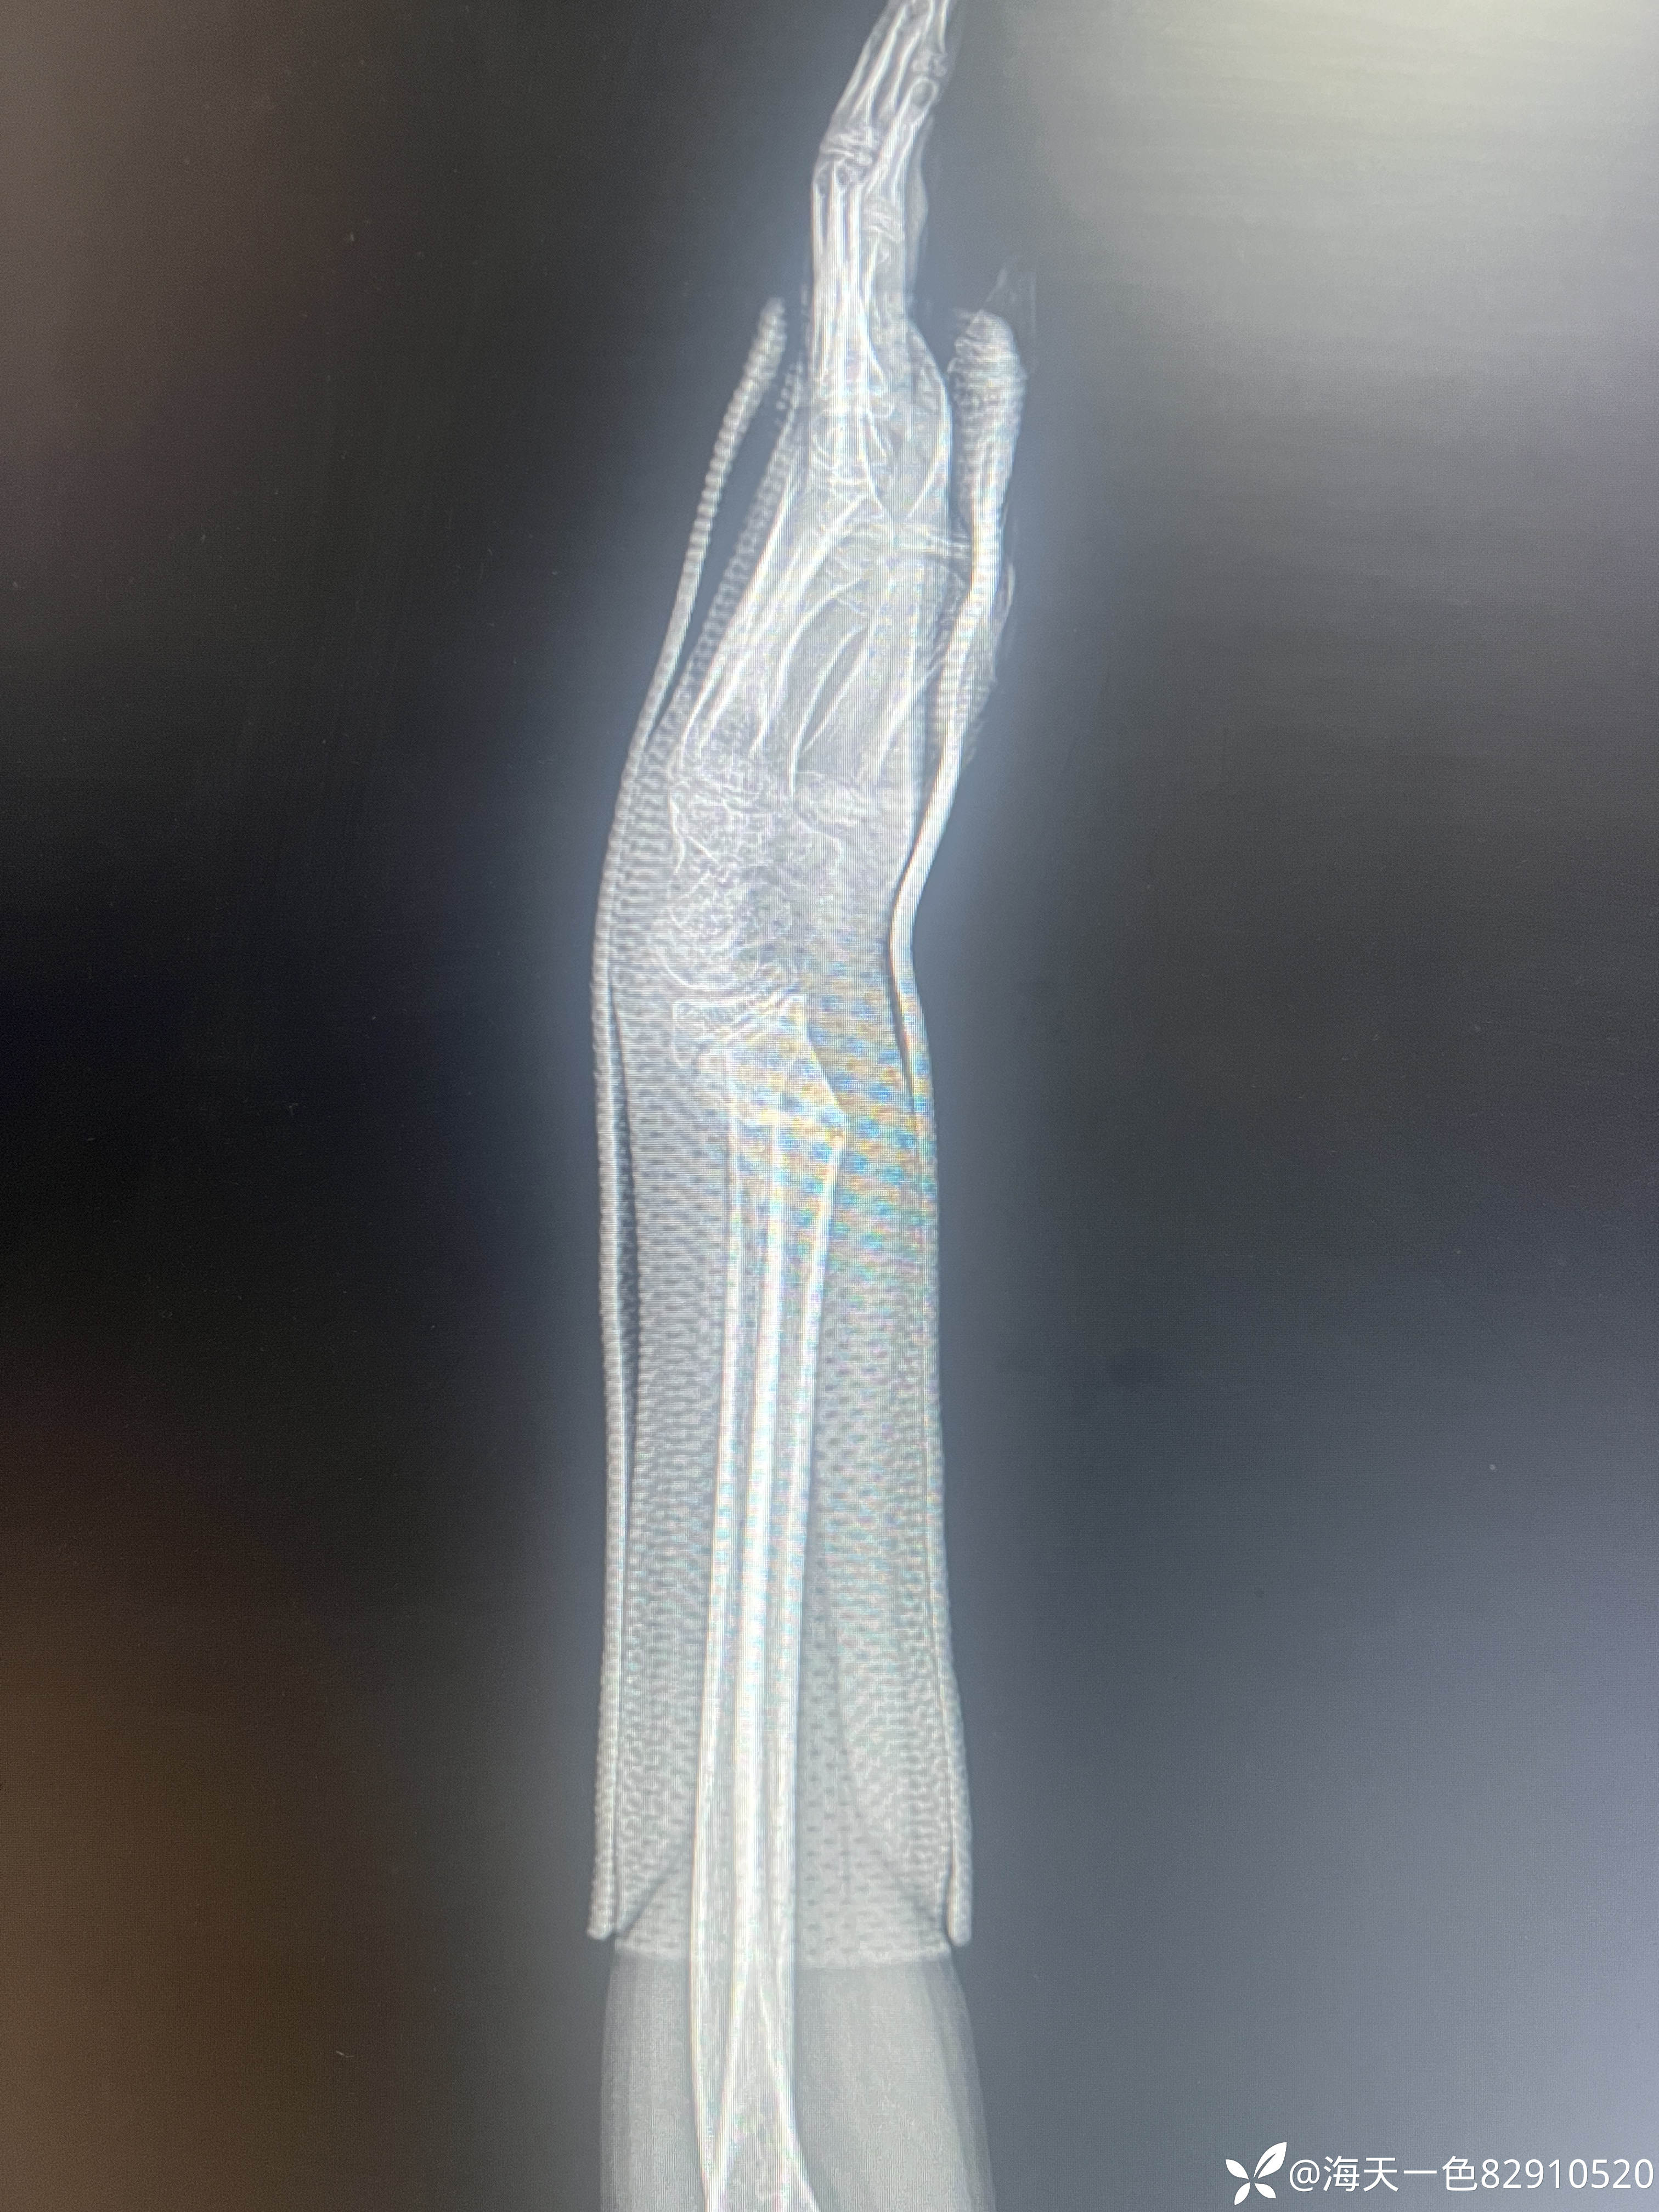

桡骨远端骨折

【患者信息】:患儿男性,14岁,

【主诉】:跑跳时不慎摔伤左腕关节肿痛14天

【临床诊断】:左桡骨远端骨折

【治疗经过及结果】:建议手术手术治疗,患儿家属未手术治疗,外院进行手法复位,复位拍片如下

移位角度有些大,预后影响大吗?